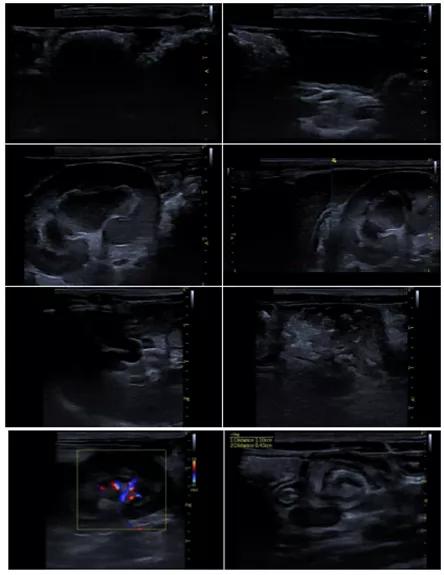

超声提示:腹水,腹膜炎,脂肪肝。

超声一月后复查腹水消失,淋巴结较上次检查减小,双肾髓质环症